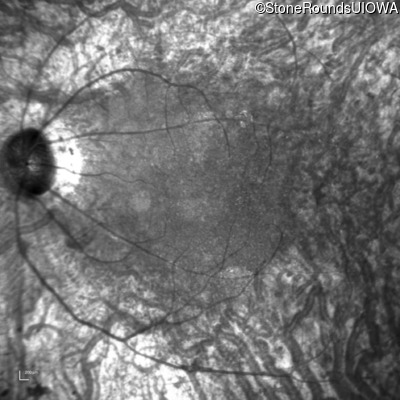

Type 2 Usher Syndrome (IB1b)

Age at visit: 53 years

This 53 year old woman first noticed night blindness at age 18. More recently she has experienced constriction of her visual fields. She has worn hearing aids since childhood.

Diagnosis & molecular findings

Disease Gene Allele 1 variant(s) Allele 2 variant(s) Inheritance mode

Type 2 Usher Syndrome ADGRV1 Arg211 del2ggcAG IVS66-2 A>T AR